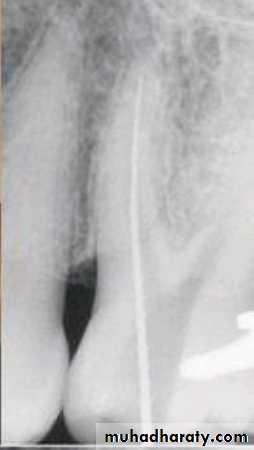

Step-back technique

MAF

WL – 0.5 mm

WL=21

SIZE=25WL=20.5

SIZE=30

WL=20

SIZE=35

WL=19.5

SIZE=40

WL=19

SIZE=45

WL=18.5

SIZE=50

WL=18

SIZE=55

WL=17.5

SIZE=60

WL=17

SIZE=70